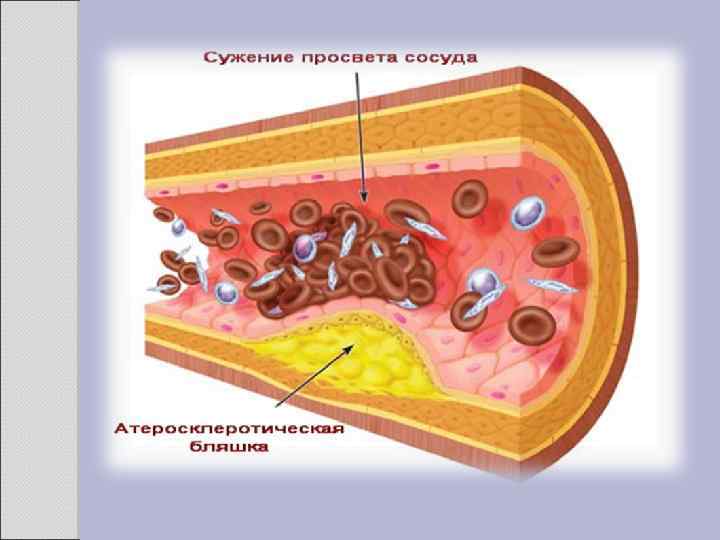

2. 1 АТЕРОСКЛЕРОЗ Атеросклероз — хроническое заболевание эластического и мышечно-эластического типа, возникающее вследствие нарушения липидного обмена и сопровождающееся отложением холестерина и некоторых фракций липопротеидов в интиме сосудов. Отложения формируются в виде атероматозных бляшек. Последующее разрастание в них соединительной ткани (склероз), и кальциноз стенки сосуда приводят к деформации и сужению просвета вплоть до облитерации (закупорки). Этиология На данный момент единой теории возникновения данного заболевания нет. Выдвигаются следующие варианты, а также их сочетания: • теория липопротеидной инфильтрации — первично накопление липопротеидов в сосудистой стенке, • теория дисфункции эндотелия — первично нарушение защитных свойств эндотелия и его медиаторов, • аутоиммунная — первично нарушение функции макрофагов и лейкоцитов, инфильтрация ими сосудистой стенки, • моноклональная — первично возникновение патологического клона гладкомышечных клеток, • вирусная — первично вирусное повреждение эндотелия (герпес, цитомегаловирус и др. ), • перекисная — первично нарушение антиоксидантной системы, • генетическая — первичен наследственный дефект сосудистой стенки, • хламидиозная — первичное поражение сосудистой стенки хламидиями, в основном, Chlamydiapneumoniae. • гормональная — возрастное повышение уровня гонадотропных и адренокортикотропных гормонов приводит к повышенному синтезу строительного материала для гормонов-холестерина.

Клиника Клинические проявления часто не соответствуют морфологии. При патологоанатомическом вскрытии обширное и выраженное атеросклеротическое поражение сосудов может оказаться находкой. И наоборот, клиника ишемии органа может появляться при умеренной облитерации просвета сосуда. Характерно преимущественное поражение определенных артериальных бассейнов. От этого зависит и клиническая картина заболевания. Поражение коронарных артерий постепенно приводит к коронарной недостаточности, проявляющейся ишемической болезнью сердца. Заинтересованность церебральных артерий вызывает либо преходящую ишемию мозга либо инсульты. Поражение артерий конечностей — причина перемежающейся хромоты и сухой гангрены. Атеросклероз брыжеечных артерий ведет к ишемии и инфаркту кишечника (мезентериальный тромбоз). Также возможно поражение почечных артерий с формированием почки Голдблатта. Даже в пределах отдельных артериальных бассейнов характерны очаговые поражения — с вовлечением типичных участков и сохранностью соседних. Так, в сосудах сердца окклюзия наиболее часто возникает в проксимальном отделе передней межжелудочковой ветви левой коронарной артерии. Другая типичная локализация — проксимальный отдел почечной артерии и бифуркация сонной артерии. Некоторые артерии, например внутренняя грудная, поражаются редко, несмотря на близость к коронарным артериям и по расположению, и по строению. Атеросклеретические бляшки часто возникают в бифуркации артерий — там, где кровоток неравномерен; иными словами, в расположении бляшек играет роль локальная гемодинамика (см. патогенез).